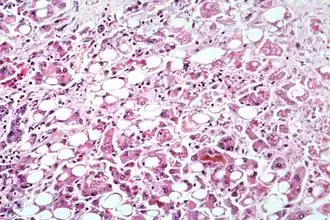

Hepatita este o boală infecțioasă de natură virală, microbiană sau toxică a ficatului care constă în distrugerea celulelor hepatice. Există mai multe forme ale bolii ca: Hepatită A, Hepatită B, Hepatită C, Hepatită D, Hepatită E, Hepatită F, Hepatită G. Indiferent de agentul cauzal, boala se manifestă la început prin simptome nespecifice, uneori febră ușoară, lipsa apetitului, emeză (grețuri, vomitări), scăderea randamentului fizic și psihic, ca și dureri abdominale, urina devine de culoare închisă, fecalele de culoare deschisă și apar forme icterice. Boala produce de regulă în final ciroză, sau cancer de ficat. După incindența bolii, România se află printre primele locuri în Europa, din cauza costului ridicat al tratamentului, conform programului Casei Naționale de Sănătate, numai 1% din bolnavi sunt tratați cu medicație antivirală.[3]